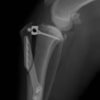

術後写真

手術前後のTPA(脛骨高平部の角度)を測定しています。

約29°から約10°へ矯正されています。